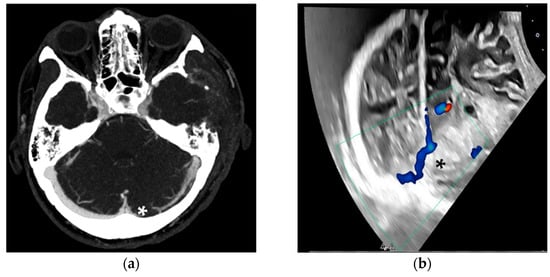

4.5. Selected Cases and Special Indications for TUS

During inpatient treatment, TUS was applied to address alternative clinical questions. In the first case, a 42-year-old female patient suffered a transverse sinus thrombosis with subsequent venous hemorrhage. Due to rapid deterioration of consciousness, the need for intubation, and a space-occupying hemorrhage, a decompressive hemicraniectomy was performed. With fluctuating intracranial pressure (ICP) peaks, follow-up imaging was primarily conducted using ultrasound. The occluded transverse sinus could be visualized daily (Figure 8).

Figure 8.

Venous CT angiography (a) and duplex ultrasound (b), both showing the occluded transverse sinus (*). The patient was later extubated, underwent cranioplasty, and recovered well. In our setting, TUS proved useful for visualizing the larger venous vessels, particularly in cases of elevated ICP, without requiring lowering the upper body for CT imaging.

In the second case, a patient experienced a SAH due to a ruptured basilar tip aneurysm. The aneurysm was treated with coil embolization and a Y-stent. Given the early postoperative period, dual antiplatelet therapy was not feasible. Ultrasound was used to monitor the patency of the stent and to exclude in-stent thrombosis (Figure 9).

Figure 9.

Digital subtraction angiography (a) and duplex ultrasound (b) of the basilar artery treated with a Y-stent. Clear perfusion is visible in the duplex ultrasound, and in this case, the need for follow-up CT angiography to rule out arterial occlusion was avoided. This patient also recovered well and was soon transferred to rehabilitation.